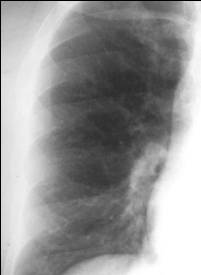

Increased Flow